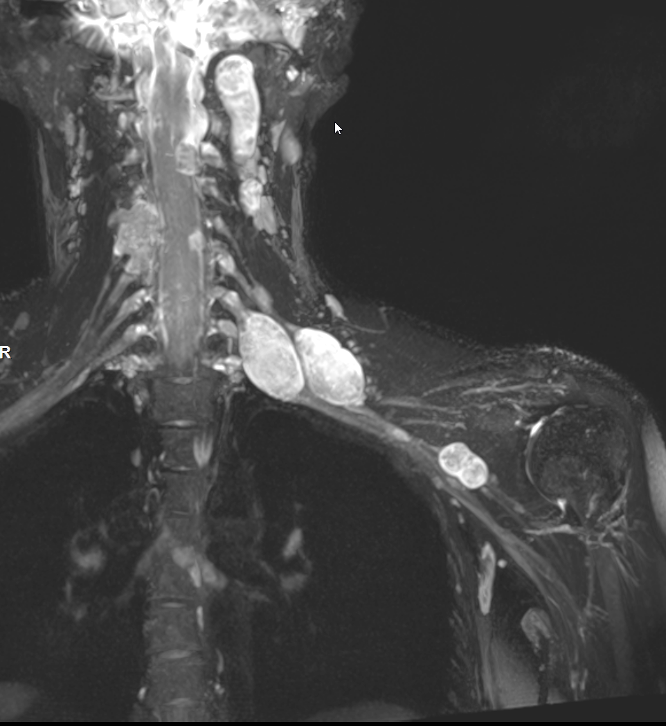

Neurofibroma brachial plexus

Target sign

- hypointense centrally

- hyperintense peripherally